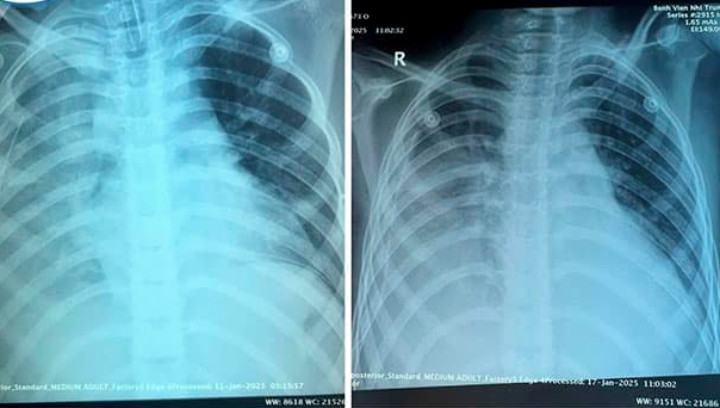

Ảnh phim chụp X-Quang phổi của trẻ trước và sau 7 ngày điều trị. (Ảnh: BVCC)

Theo PGS.TS Tạ Anh Tuấn – Trưởng khoa Điều trị tích cực Nội khoa, Bệnh viện Nhi Trung ương, khi nhập viện, tình trạng của bệnh nhi khá nặng với chẩn đoán viêm phổi hoại tử, viêm mủ màng phổi, theo dõi nhiễm khuẩn huyết.

Nhờ được điều trị và chăm sóc tích cực, 10 ngày sau phẫu thuật, bệnh nhi cai máy thở và cai dần oxy. Ngày 28/1 (tức 29 Tết), sau 20 ngày điều trị, trẻ phục hồi tốt và được xuất viện.